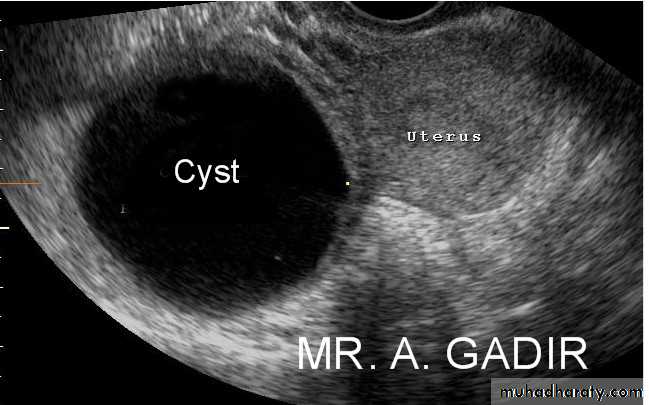

Hemorrhagic cyst of ovary with ruptured ectopic pregnancy:

This female patient has a left ovarian hemorrhagic cyst (see ultrasound image above-left). In addition, there is a large collection of free fluid with particulate matter in the pelvis. The right fallopian tube is thickened with a ring shaped mass. This suggests that there is significant hemorrhage into the pelvis due to a ruptured ectopic pregnancy (right tubal ectopic gestation). The left ovarian hemorrhagic cyst appears intact, ruling out ruptured hemorrhagic cyst.